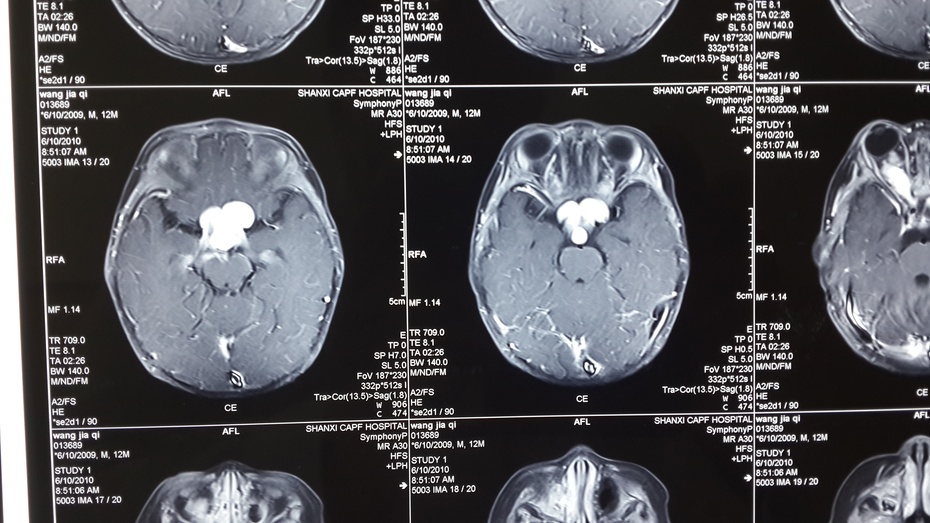

贺教授检查,发现孩子大大的眼睛,红红的脸颊,亮黑但显得较大的瞳仁。孩子头颅MRI增强扫描显示:双侧视神经增粗、视交叉成结节状。诊断:视神经胶质瘤。是神经胶质瘤因该如何治疗呢?!